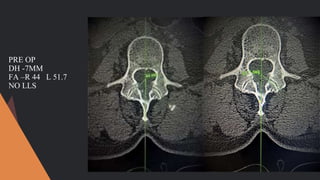

PRE OP

DH -7MM

FA –R 44 L 51.7

NO LLS

PRE OP DH -7MM FA–R 44 L 51.7 NO LLS